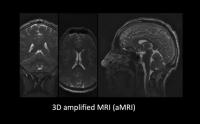

Beating brain

video: 3D aMRI not only provides a stunning look inside the "beating brain", but it can also measure this physiological motion in all directions. Here, the amplitude of brain motion is overlayed for each brain slice and orientation in 3D view more

Credit: 3D aMRI method outlined in Abderezaei et al. Brain Multiphysics (2021); Terem et al. Magnetic Resonance in Medicine (2021).

The new technique, called 3D amplified MRI, or 3D aMRI, reveals pulsating brain movement which could help researchers to non-invasively visualise brain disorders and inform better treatment strategies for tiny deformations or disorders that obstruct the brain or block the flow of brain fluids.

3D aMRI of the human brain shows minute movements of the brain at an unprecedented spatial resolution of 1.2mm3, approximately the width of a human hair. The actual movements are amplified (made larger, up to 25 times) to allow clinicians and researchers to view the movements in detail. The striking detail of these animated magnified movements may be able to help identify abnormalities, such as those caused by blockages of spinal fluids, which include blood and cerebrospinal fluid.